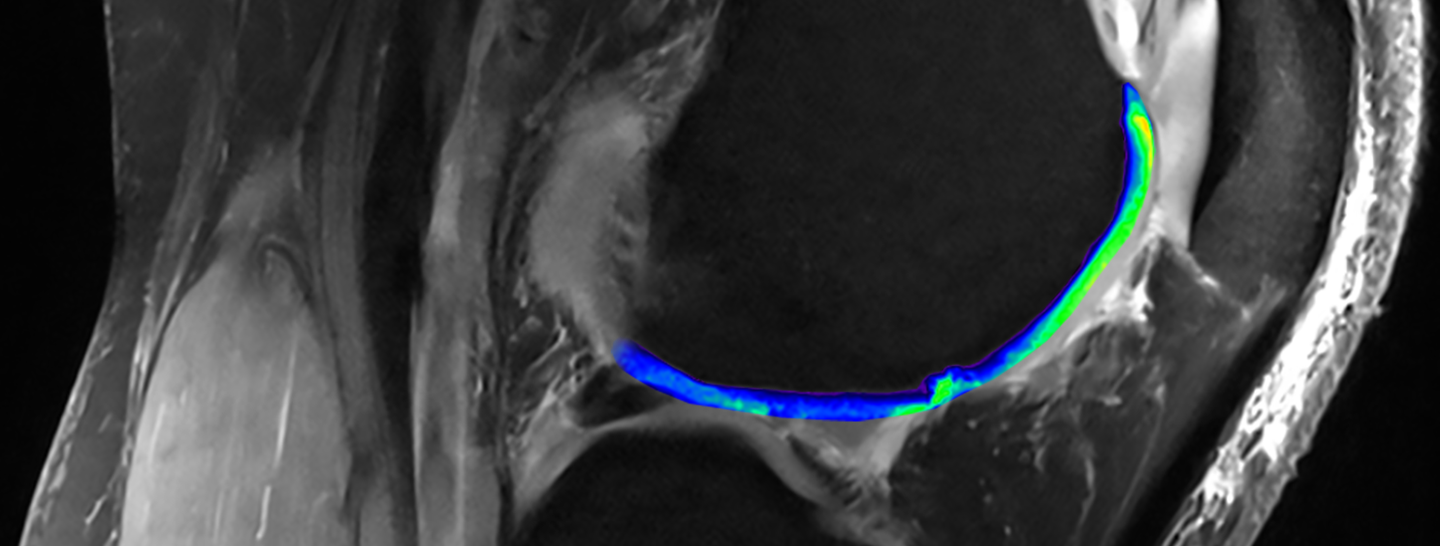

Imagerie IRM du genou

Les appareils d’IRM traditionnels utilisent des impulsions magnétiques afin de recueillir le signal des molécules d’eau (hydrogène) contenues dans l’organisme. Cette technologie permet de distinguer visuellement le cartilage (en bleu/vert clair) des os. Si les appareils d’IRM modernes ont recours au même procédé, ils se concentrent sur le sodium et non sur l’hydrogène. Ceci permet de mettre en évidence les protéoglycanes (en vert clair), un composant propre au cartilage sain. L’absence de signal sodique dans certaines régions indique ainsi qu’elles sont concernées par un dysfonctionnement du cartilage. Photos publiées avec l’aimable autorisation de Siegfried Trattnig (modifiées par Fidelis Onwobueke)

Outre le recours à un puissant appareil d’IRM, Siegfried Trattnig a également mis au point des techniques qui élargissent le spectre des matériaux pouvant être analysés par ces équipements. Ainsi, ils sont par exemple en mesure de déterminer le taux de protéoglycanes, un composant propre au cartilage sain.

Ces clichés d’IRM montrent également les fissures du cartilage (bleu foncé, en haut), signe d’une dégradation. Les chercheurs des NIBR tentent de trouver un moyen de combler ces fentes avec du cartilage sain dans le cadre d’expériences relevant de la médecine régénérative. Grâce à l’utilisation d’appareils d’IRM de pointe dans leurs études cliniques, ils sont parvenus à mesurer la qualité du cartilage régénéré – et ce, sans que les patients soient contraints de se soumettre à de douloureuses biopsies.